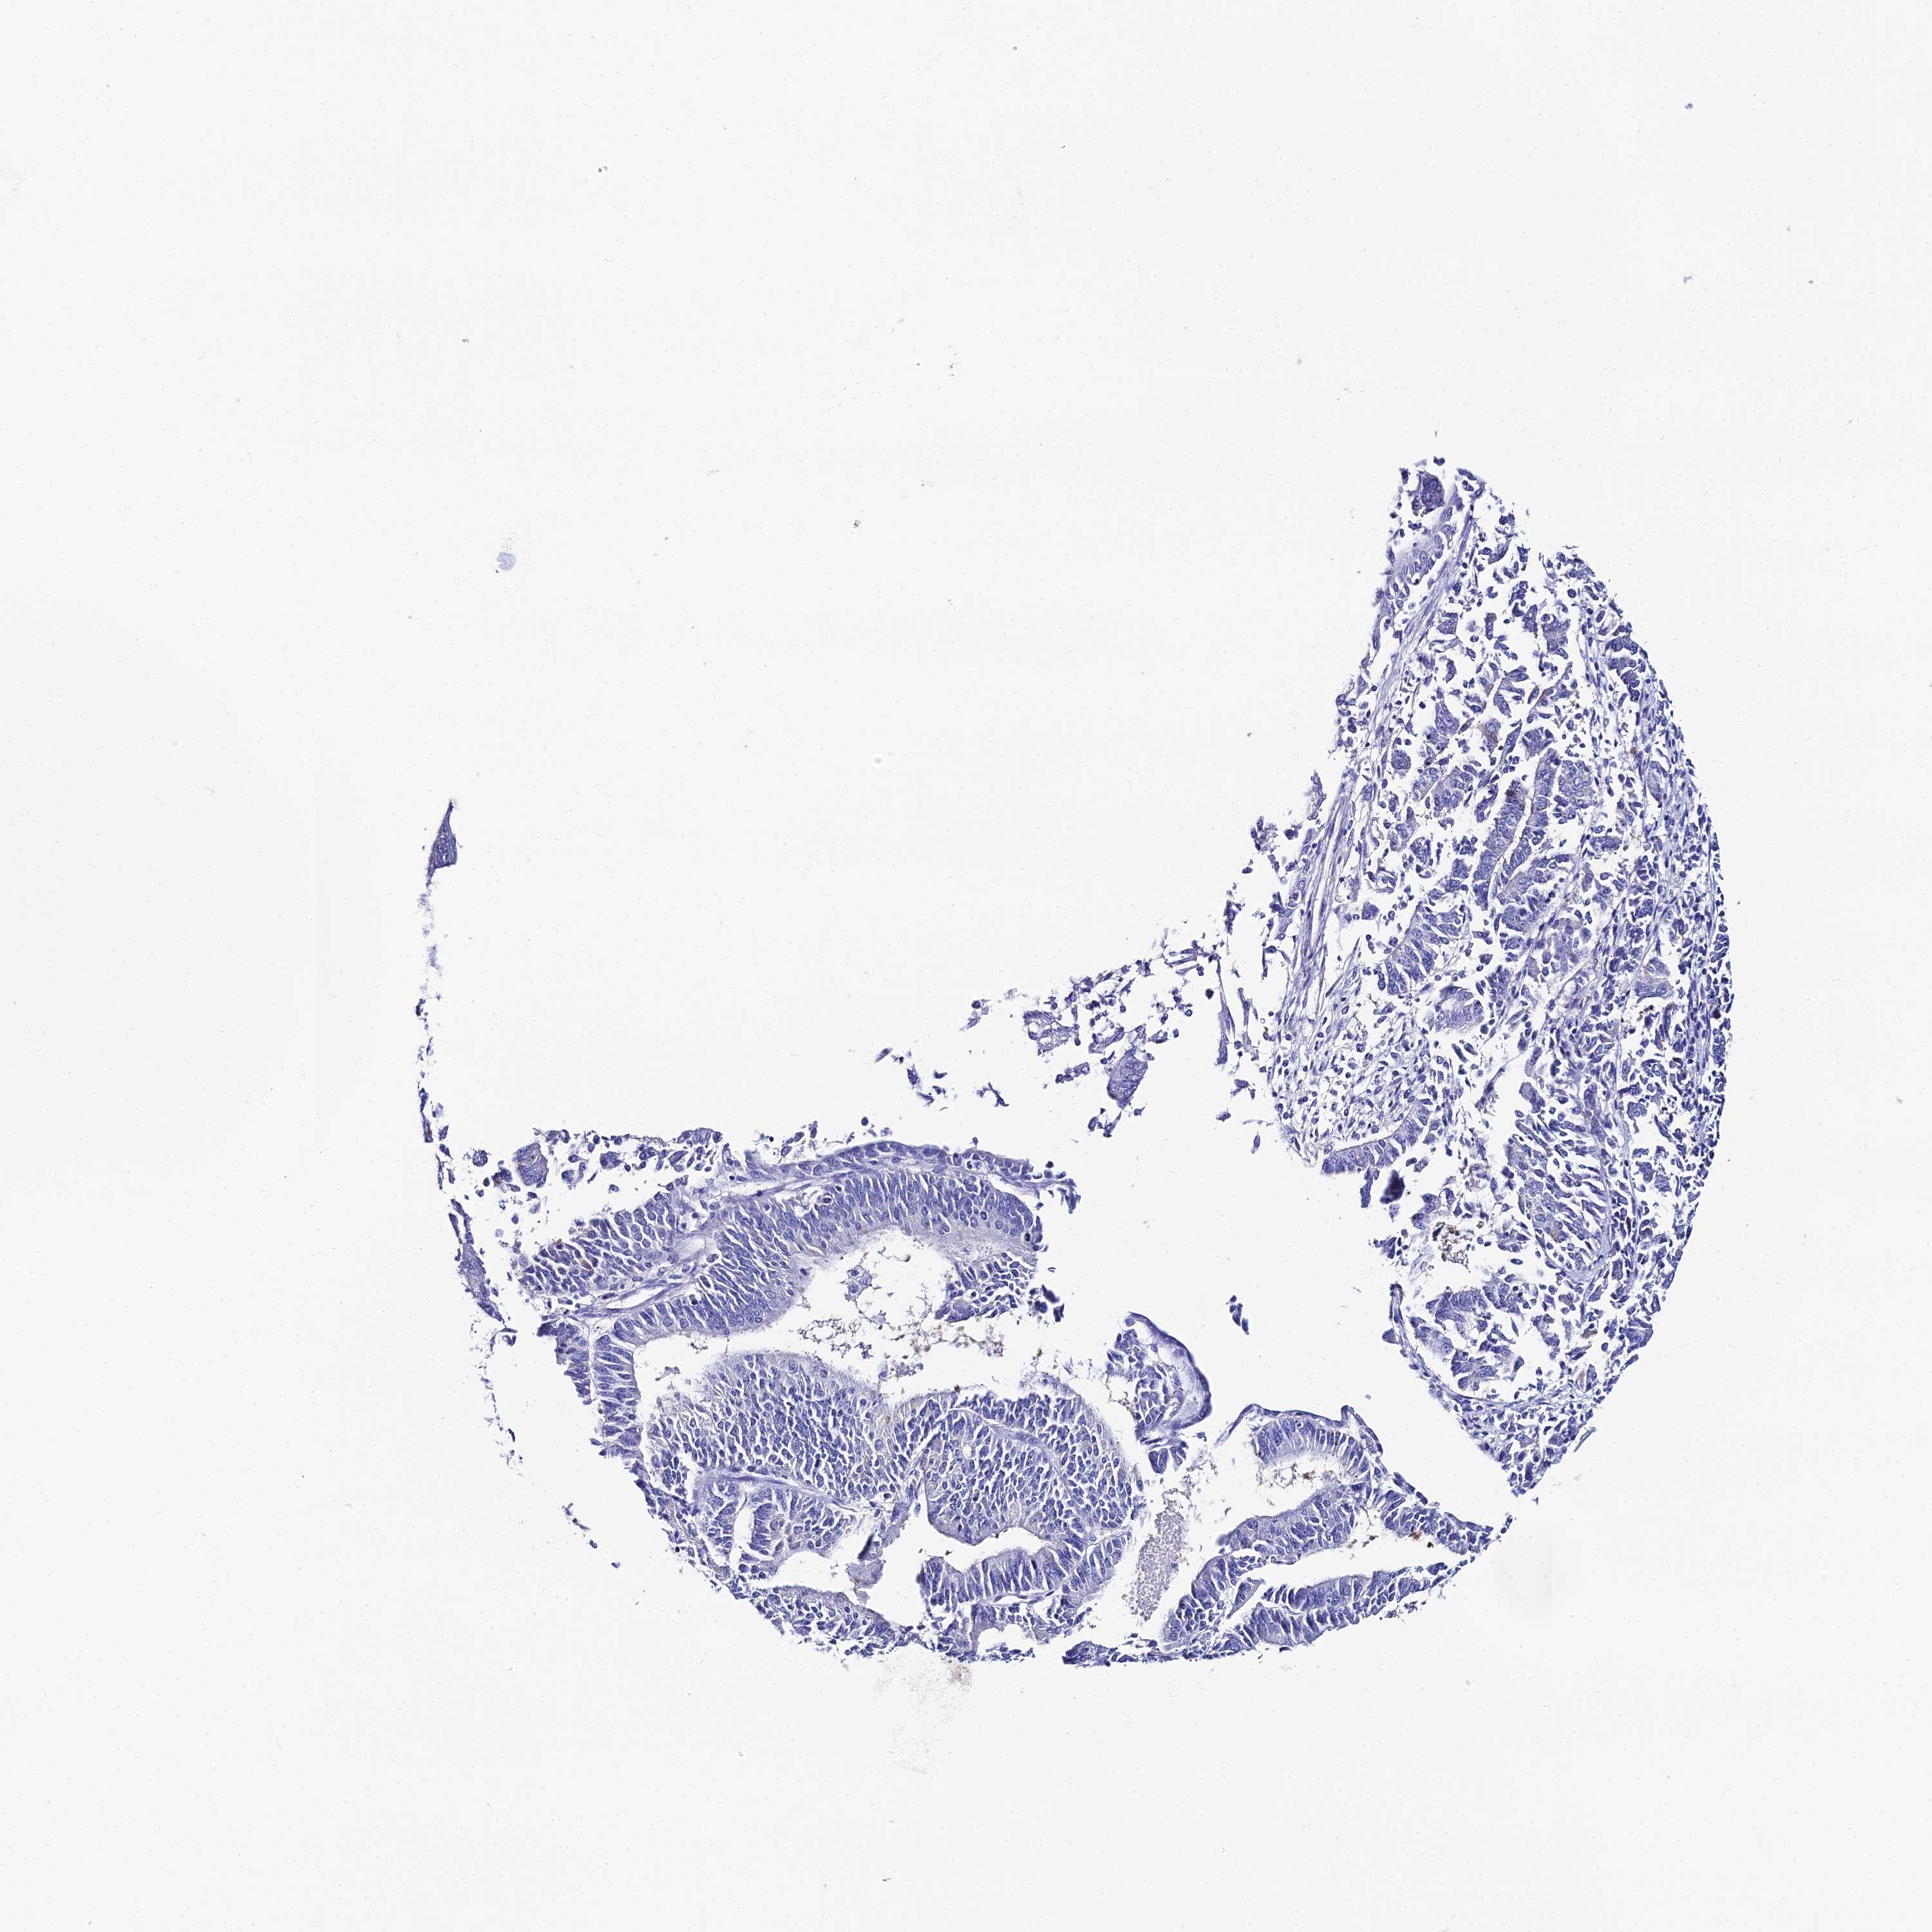

ENDOMETRIAL CANCER - Protein expressioni

A mouse-over function shows sample information and annotation data. Click on an image to view it in a full screen mode. Samples can be filtered based on level of antibody staining by selecting one or several of the following categories: high, medium, low and not detected. The assay and annotation is described here.

Note that samples used for immunohistochemistry by the Human Protein Atlas do not correspond to samples in the TCGA dataset.

Antibody stainingi

Antibody staining in the annotated cell types in the current human tissue is reported as not detected, low, medium, or high, based on conventional immunohistochemistry profiling in selected tissues. This score is based on the combination of the staining intensity and fraction of stained cells.

Each image is clickable and will lead to virtual microscopy that enables deeper exploration of all samples and also displays staining intensity scores, fraction scores and subcellular localization as well as patient and tissue information for each sample.

Antibody HPA043285

Antibody HPA052504

Staining

High

Medium

Low

Not detected

Intensity

Strong

Moderate

Weak

Negative

Quantity

>75%

75%-25%

<25%

None

Location

Nuclear

Cytoplasmic/membranous

Cytoplasmic/membranous,nuclear

Adenocarcinoma, NOS

Adenocarcinoma, metastatic, NOS

Carcinoma, NOS